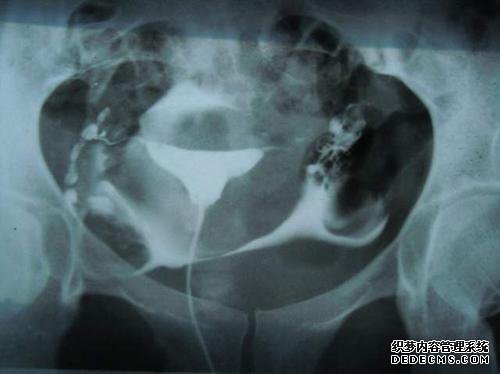

在常规的子宫输卵管血管造影术中,在将造影剂注射入子宫腔后使用球囊导管插入造影剂时,在填充造影剂后,使用宫颈钳来固定和牵拉子宫颈充满气球可能会露出子宫腔的一半以上,引起不同程度的疼痛和不适,导致精神紧张和麻痹,然后出现假阳性。

另外,使用球囊导管进行子宫输卵管造影术可能会阻塞子宫腔内的粘连和息肉,并阻止观察到它们。同时,由于可以将导管向一侧挤压,因此造影剂可能无法顺利流动。因为没有造影剂,输卵管的另一侧不会发育。输卵管无法通过。

当在血管造影期间放置鞘管护套以进行无痛宫腔镜检查时,不仅需要宫颈钳,而且鞘管没有放置在子宫腔中,并且仅需要特殊的锥形橡胶导管可以用一点推力注射子宫颈,但不会在子宫腔内造成任何阻塞或阻塞,并且可以准确地反映子宫腔和输卵管,从而获得更准确的测试结果。